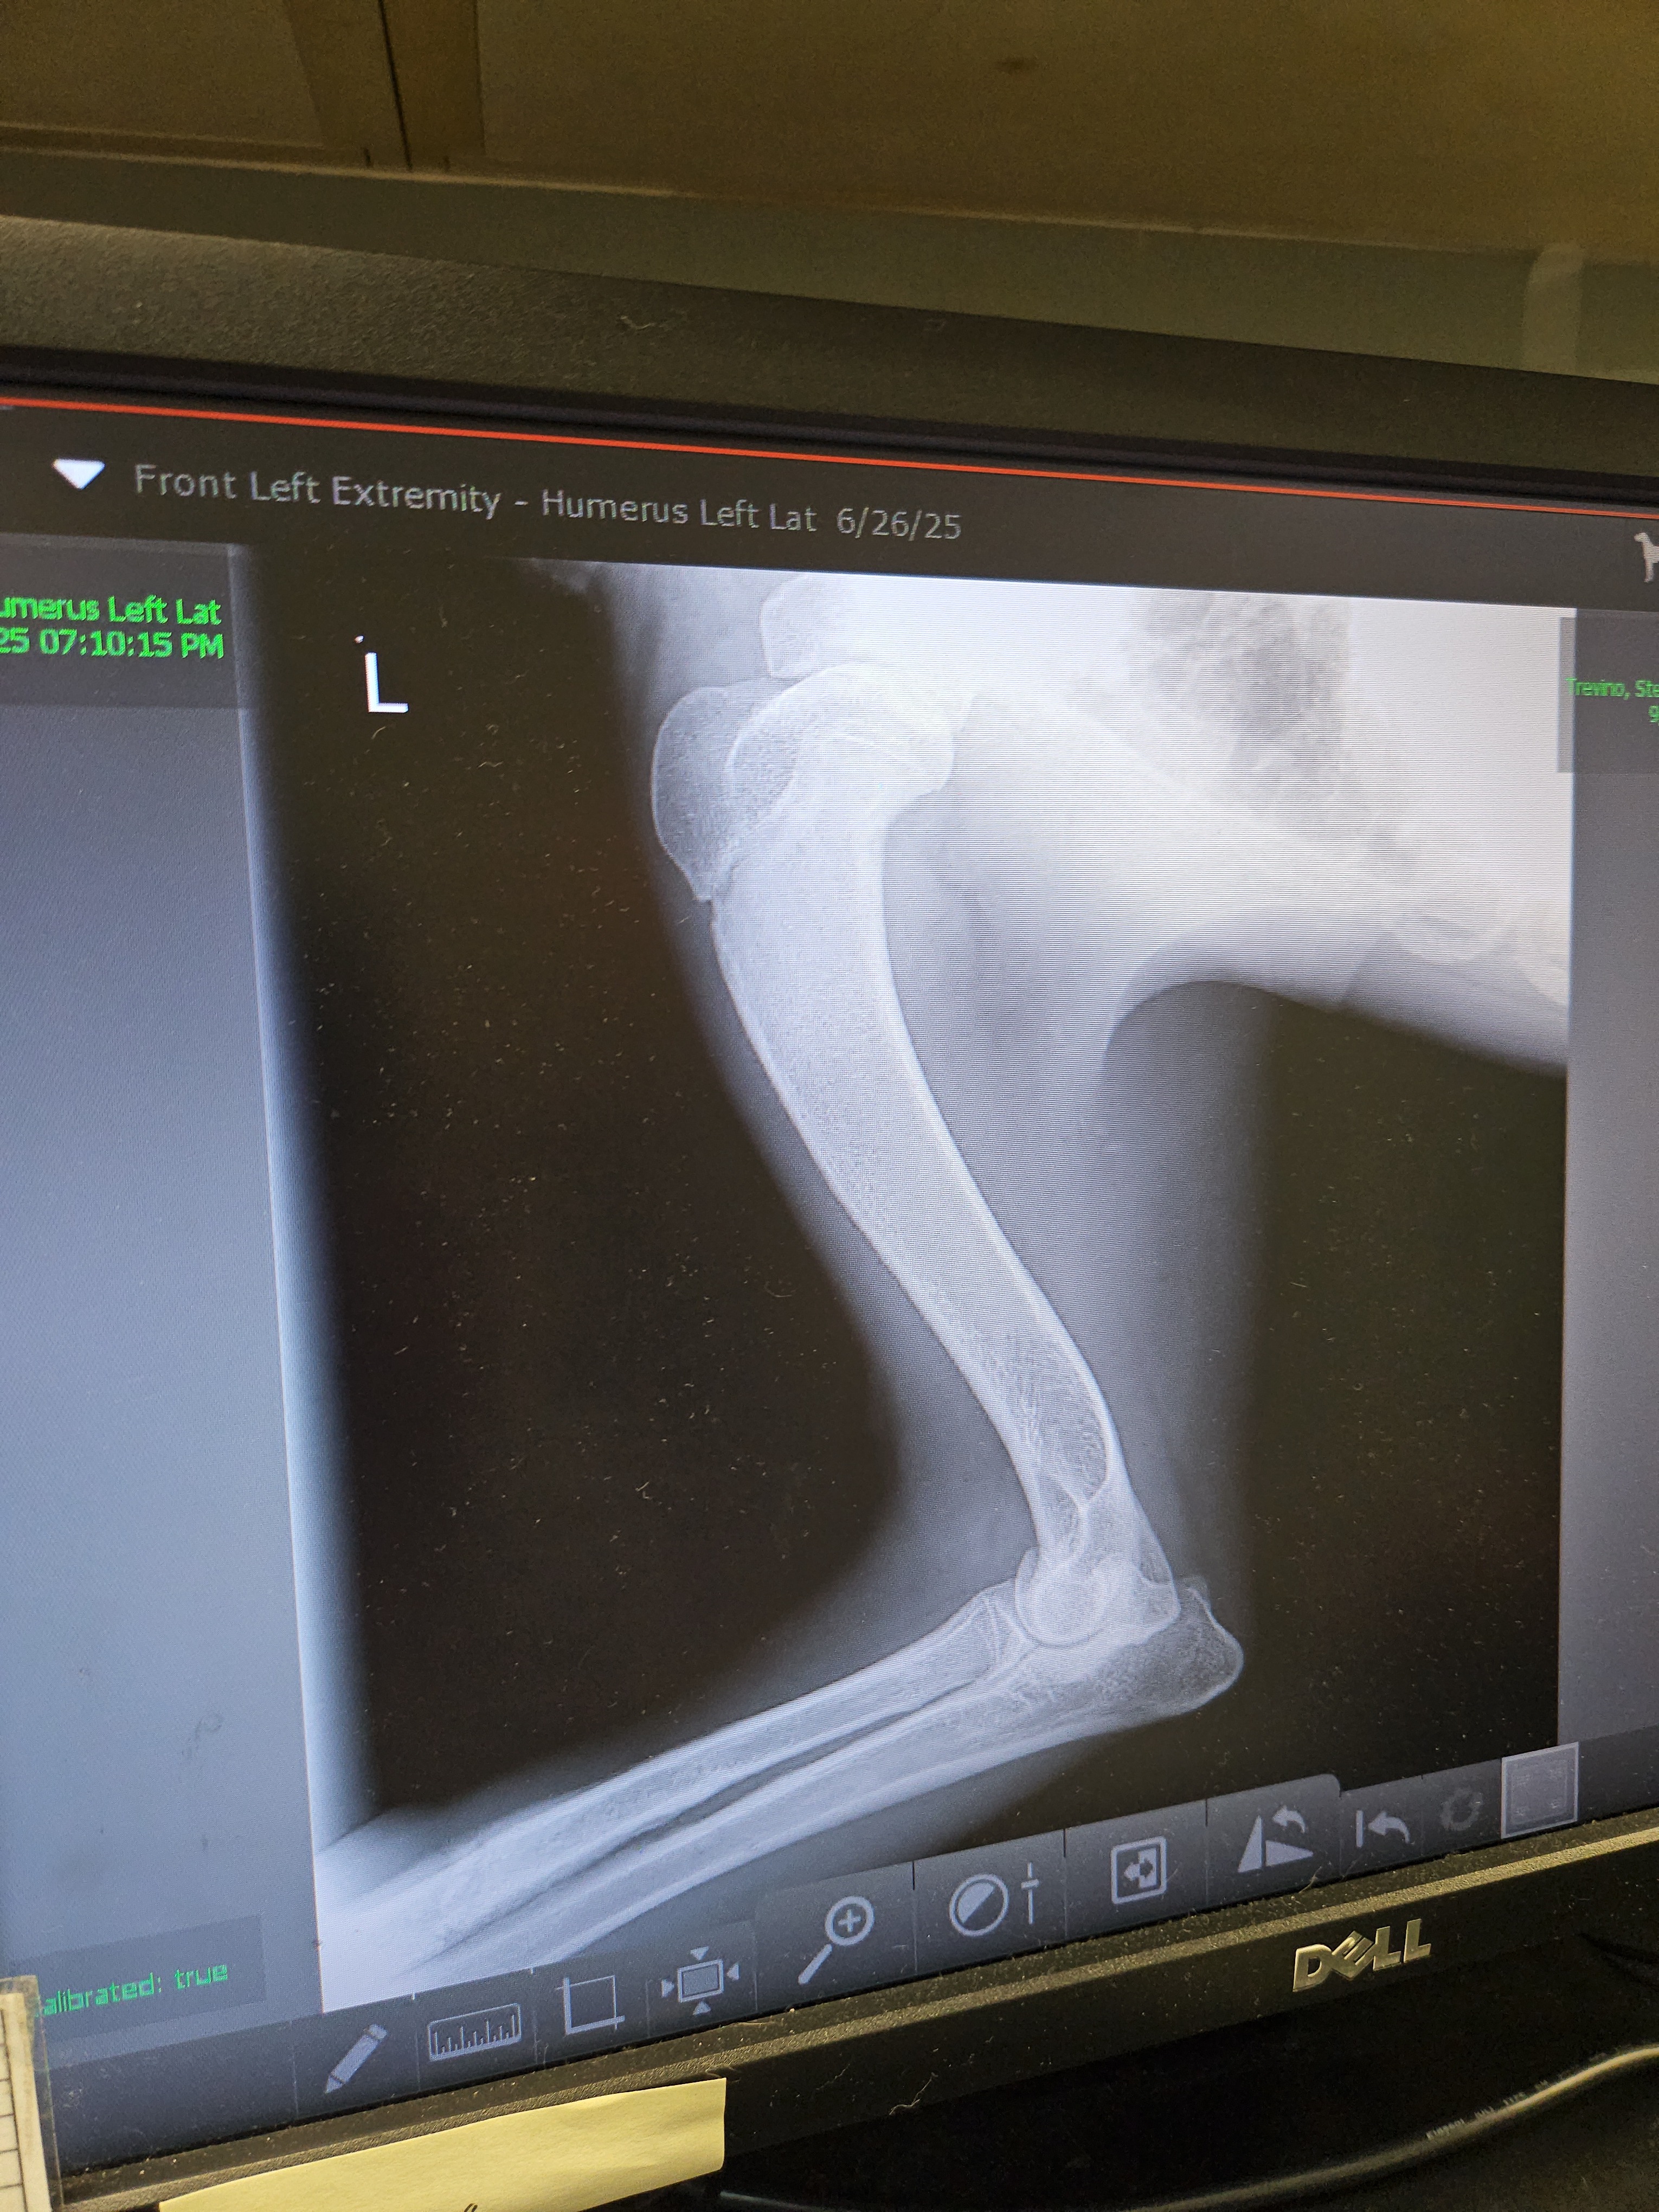

Darla is our 8-month-old Saint Bernard who escaped out of our fenced yard. She had to be trapped by a trapper who generously donated his time because she was on the run for so long. Sometime during the 14 days she was on the run, she was hit by a car, fracturing her leg and shoulder. The leg has started to heal, and the only option is going to be possible orthopedic surgery. We are fortunate enough to have some money put aside and our care credit but are still coming up short.